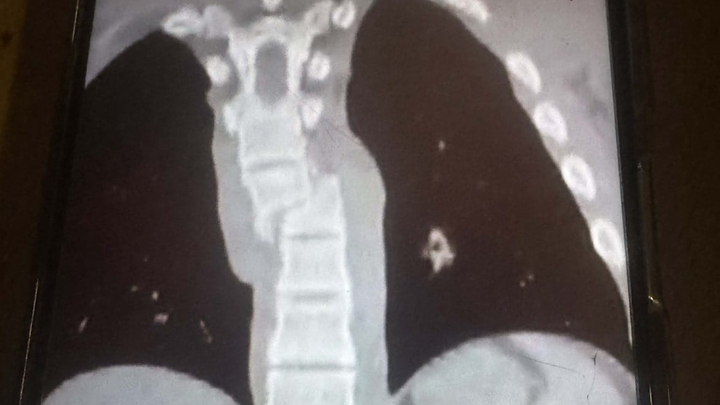

Zusätzlich erlitt er eine gebrochene Rippe und eine schwere Verletzung der Lunge. Durch ein Loch in der Lunge kam es zu weiteren Komplikationen. Seitdem liegt er auf der Intensivstation, sein Zustand ist kritisch und leider zuletzt eher schlechter als besser geworden.